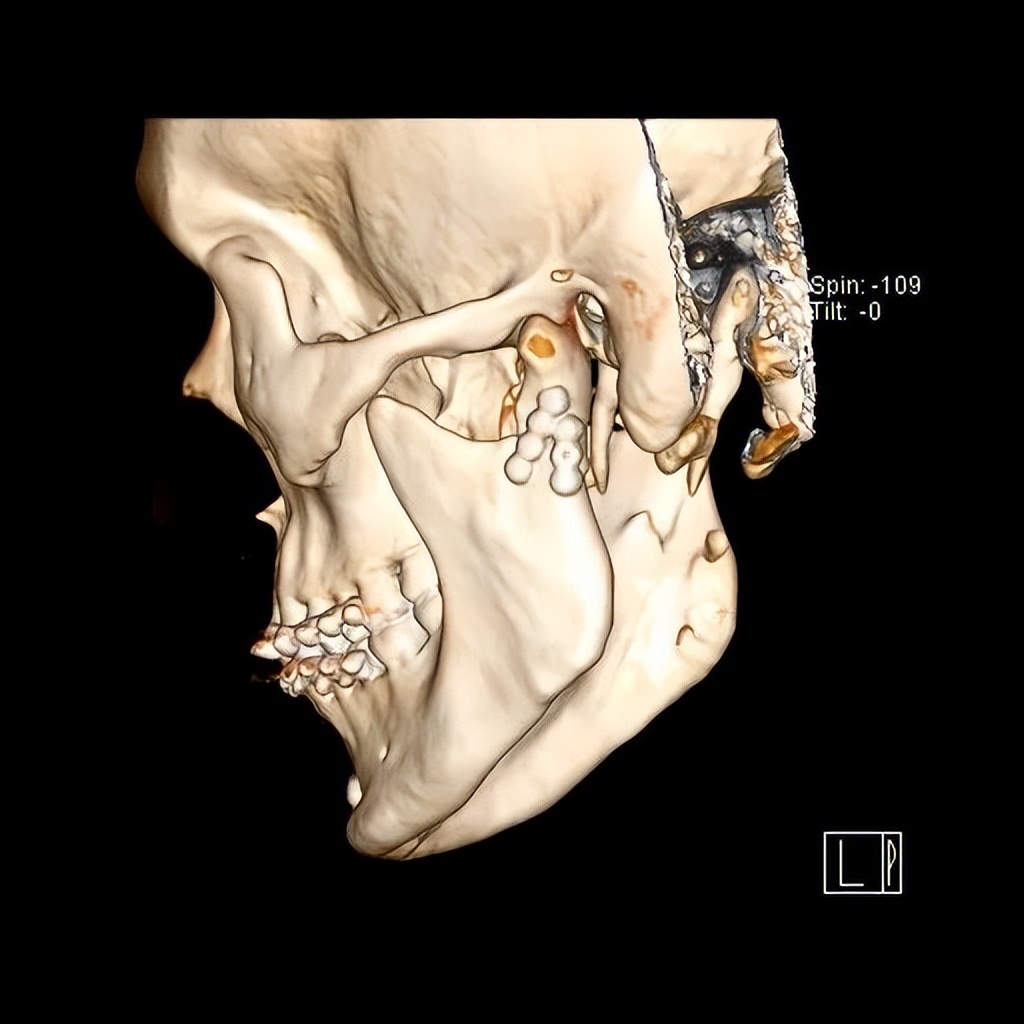

髁突骨折较一般下颌骨骨折复杂。首先,髁突参与形成颞下颌关节,该关节是人体最灵活功能最复杂的关节之一,一旦遭受损伤,可能出现咬合紊乱、张口受限、关节强直、关节炎等;由于髁突为生长发育中心,未成年人还可能影响颌面部的发育。其次,髁突骨折分类及相应治疗原则多样,根据骨折高中低位,髁突骨折可简易分为髁头、髁颈、髁基骨折,每种分类又根据移位等情况分为不同亚型,不同分类亚型需正确选择手术适应症,才能达到最佳治疗效果。第三,髁突手术涉及支配面部表情肌的运动神经-面神经,分泌唾液的大腺体-腮腺等重要解剖结构,需熟练掌握手术技巧,以避免面瘫等影响患者美观的并发症。

淄博市中心医院口腔颌面外科团队在下颌骨髁突骨折方面积累了较为丰富的治疗经验,近年来不断更新吸收先进治疗理念。近期,团队对多位合并髁突骨折的下颌骨骨折患者,按照标准治疗理念,或行手术治疗,或保守康复治疗,均取得了良好的效果。此外,为解决切口瘢痕影响美观的问题,团队医生积极开展了发际内结合耳屏后缘、耳后切口等美容切口设计,使手术切口更为隐蔽不可见,满足了年轻患者的美观需要。

术前

术后

术后切口